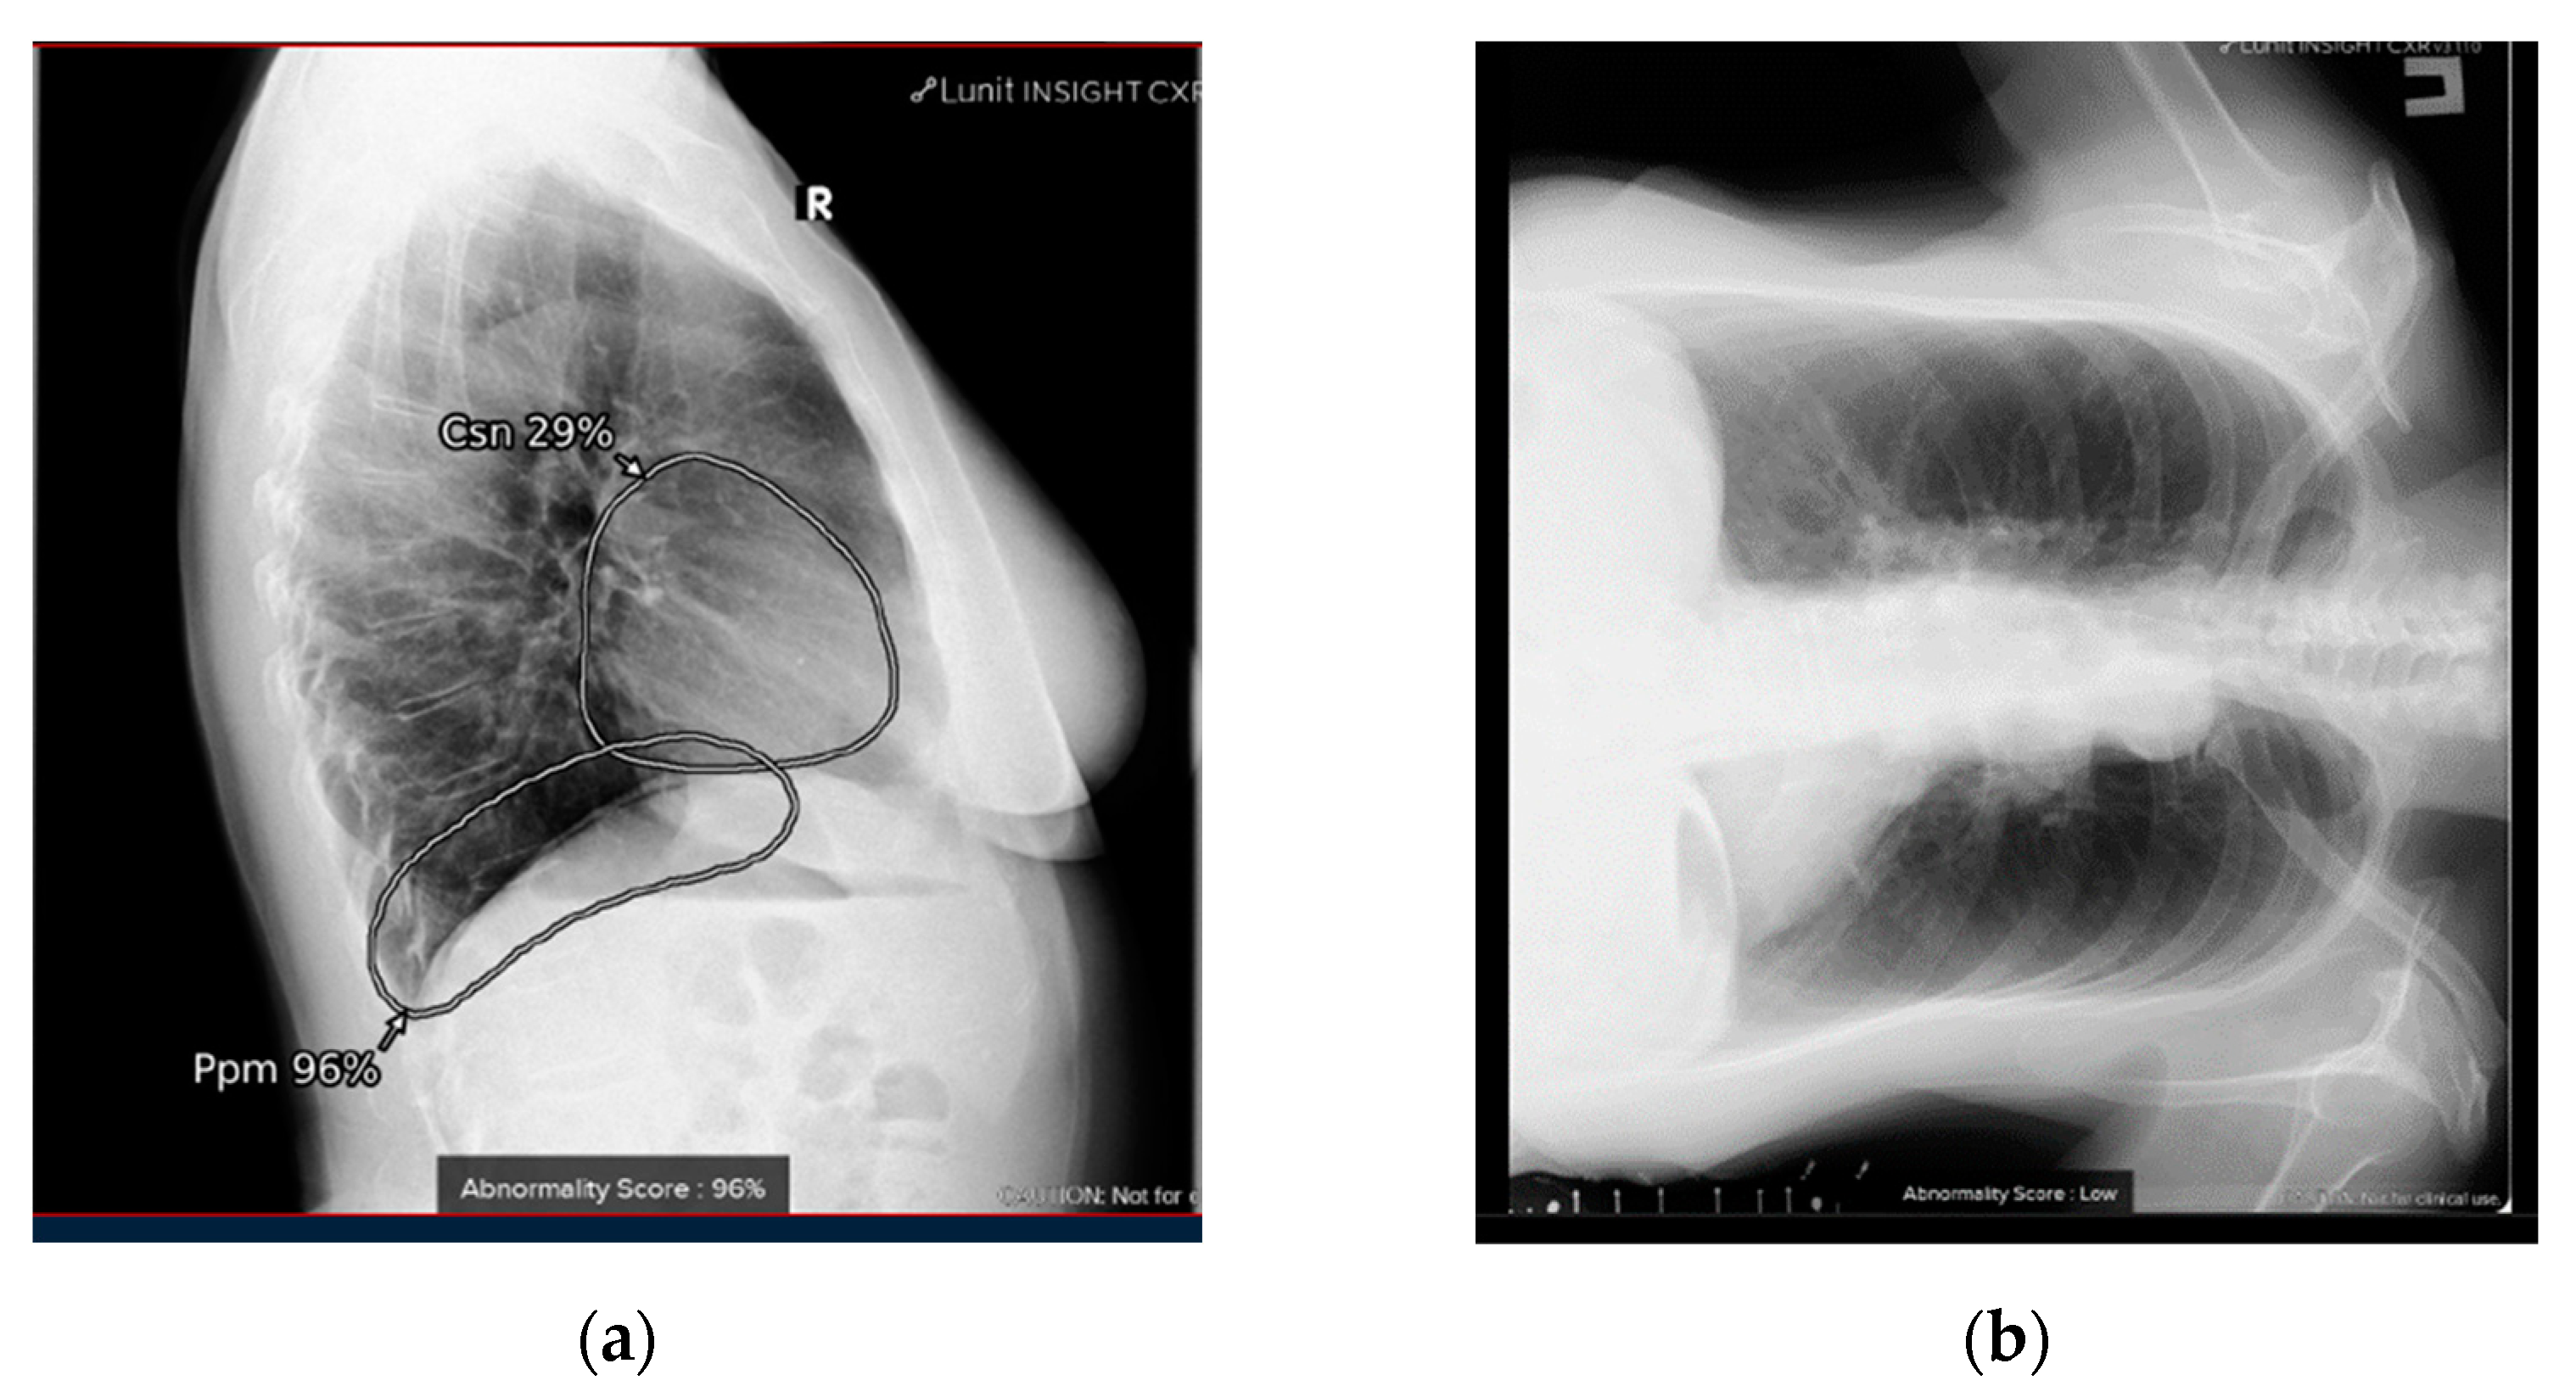

2.1. AI System

4.1. Additional Data and Technical Assessment of the Quality of Input CXR

4.2. Comprehensive Assessment of Identified Radiographic Features